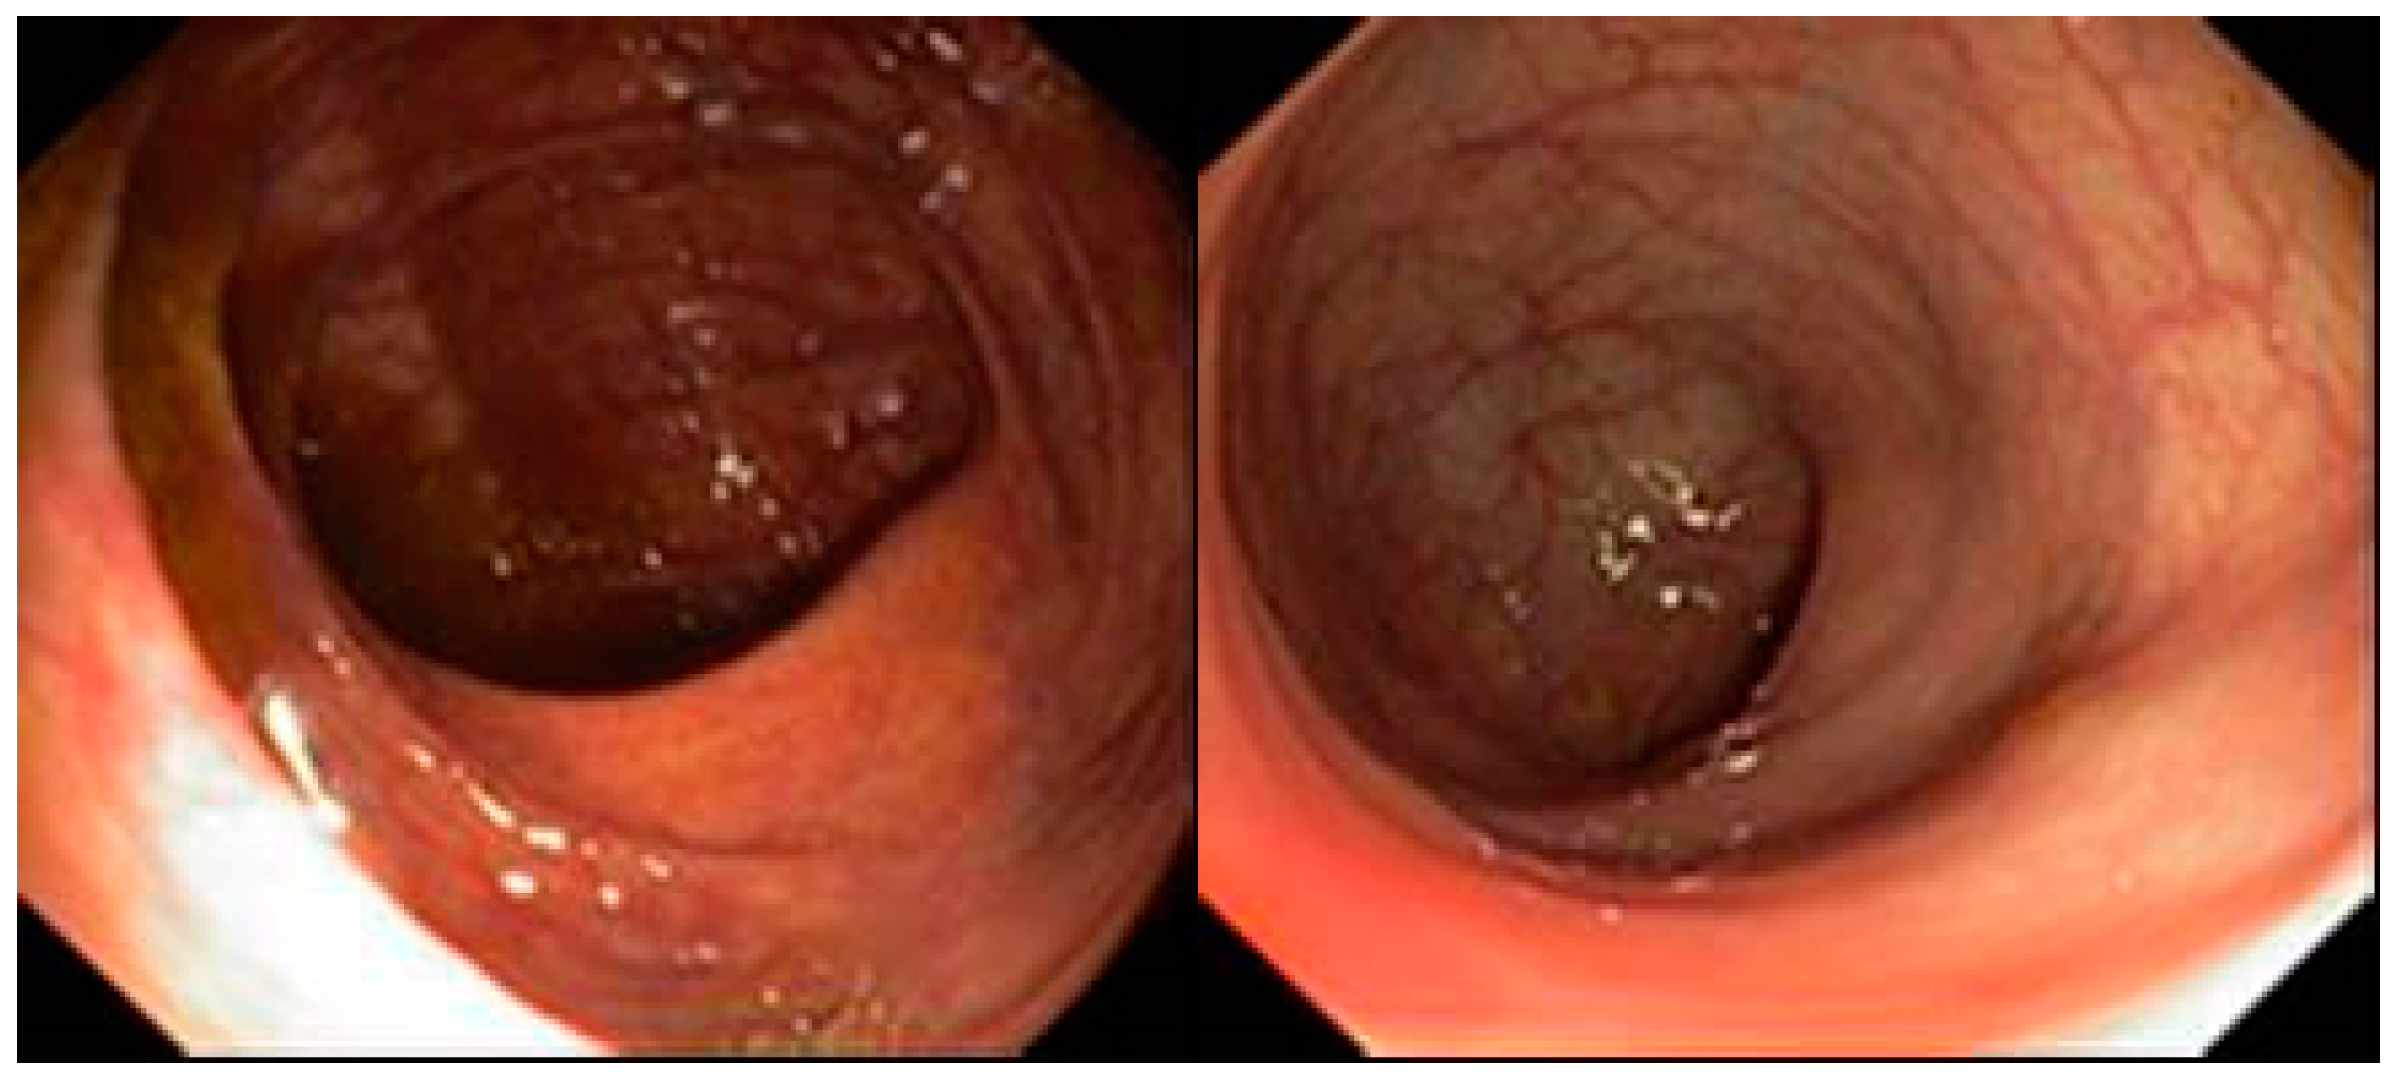

2. Case Presentation